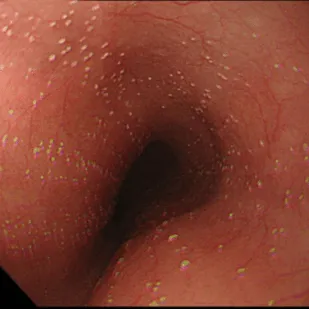

Степень III

Сливные линейные и узловатые приподнятые бляшки, с гиперемией и язвами